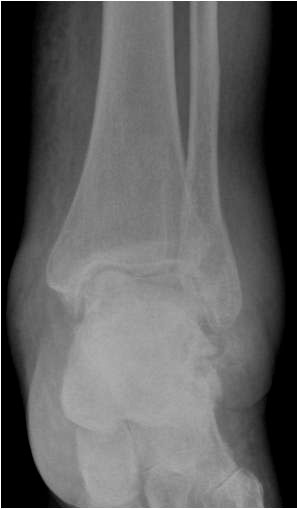

• Primäre oder posttraumatische Arthrose des OSG und USG (Abbildung 1, Abbildung 2).